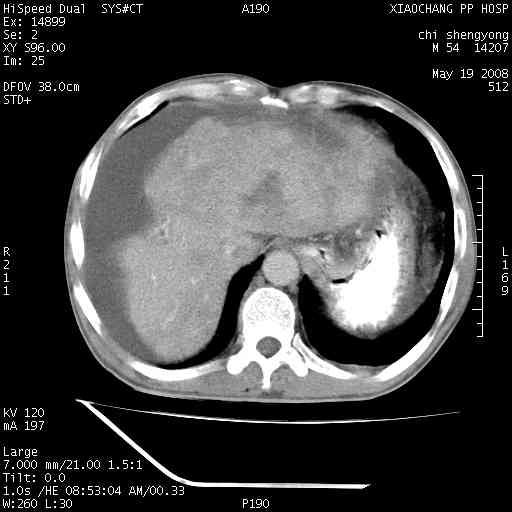

以下是引用zjzjr在2008-5-21 10:52:00的发言:[br]肝左叶巨块型肝癌伴门静脉左支瘤栓形成.肝硬化、腹水,胃底静脉曲张,脾术后改变。

以下是引用随光逐影在2008-5-21 16:20:00的发言:[br]1)肝左叶肝癌伴门静脉左支瘤栓形成,腹膜后淋巴结转移。2)肝硬化、腹水、胃底静脉曲张。3)胆囊炎。4)脾脏缺如,为切除术后所致。